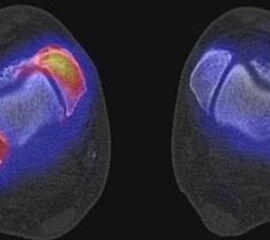

Die Abbildungen 4.2.a bis d zeigen den typischen Aspekt einer talacalcanearen Coalitio. Es besteht nur eine linksseitige, symptomatische Coalitio talocalcaneare (4.2.a und c); das 35 Tage zuvor angefertigte MRT zeigt keine auffälligen Signalveränderungen (4.2.b und d).

Abbildung 4.3. zeigt die Ursache für rechtsseitige Sprunggelenksbeschwerden bei einem Patienten mit talocalcanearen Coalitionen: nur die osteochondrale Läsion an der distalen rechten Tibia ist die Ursache des Schmerzes. Die bilateralen talocalcanearen Coalitionen sind asymptomatisch.